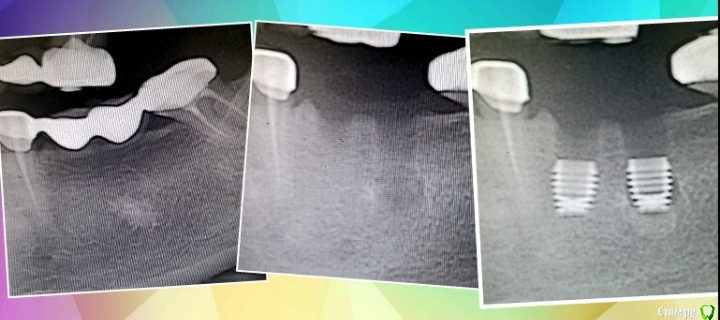

Имплантатор Опубликовано 11 июня, 2015 Поделиться Опубликовано 11 июня, 2015 Пример. Фотал телефоном из-за отсутствия времени. Удалена трепаном с со щечной стороны, поставлены имплантаты. При трепанировании получено кортикальная пластинка, которая уложена обратно. По гистологии остеома. Если пациенты спокойны и доверяют, то гистологию не отправляю, а косервирую в формалине, на всякий. Ссылка на комментарий

syrovovec Опубликовано 11 июня, 2015 Поделиться Опубликовано 11 июня, 2015 А на Rg справа что? 1 Ссылка на комментарий

doc-евгений Опубликовано 11 июня, 2015 Поделиться Опубликовано 11 июня, 2015 А на Rg справа что?Два имплантата байкон, сильно заглубленные, Ссылка на комментарий

Имплантатор Опубликовано 12 июня, 2015 Поделиться Опубликовано 12 июня, 2015 Два имплантата байкон, сильно заглубленные,Заглубление оптимально, с учетом последующей резорбции составит около 3 мм. Единственное отхождение от протокола - это выбор другого размера дистального имплантата, нежели это рекомендуется. Кортикальная трепанированная пластинка послужила клином для стабилизации имплантата. Ссылка на комментарий

Имплантатор Опубликовано 12 июня, 2015 Поделиться Опубликовано 12 июня, 2015 Когда нет возможности аугментации, применяю байкон. Для нестандартных случаев. Со щечной стороны глубина около 2 мм, с апрокс. До 5 мм. При заживлении и ремоделировпнии сглаживается Ссылка на комментарий